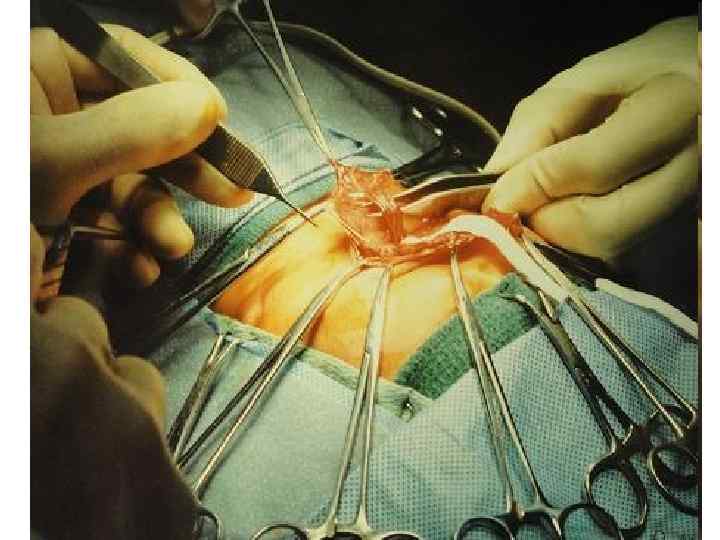

120

121